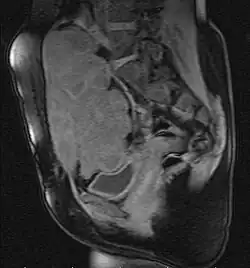

![]() Guz desmoidalny w jamie brzusznej, rezonans magnetyczny | |

Podejrzenie guza desmoidalnego jest stawiane na podstawie badań obrazowych, z których największe znaczenie kliniczne ma rezonans magnetyczny. Ostateczne rozpoznanie wymaga pobrania biopsji guza i oceny histopatologicznej[4].

- Rezonans magnetyczny

Rezonans magnetyczny (MRI) jest podstawową metodą obrazowania wykorzystywaną w diagnostyce, planowaniu leczenia oraz ocenie odpowiedzi na leczenie guza desmoidalnego[50]. W porównaniu do tomografii komputerowej metoda oferuje dokładniejsze odwzorowanie tkanek miękkich, co pozwala na lepsze określenie stosunku guza do sąsiednich ważnych struktur, w tym naczyń, nerwów, mięśni oraz narządów wewnętrznych[50].

Wzór sygnału guza desmoidalnego w pewnym stopniu koreluje z obrazem histopatologicznym i różni się w zależności od stosunku fibroblastów do zrębu kolagenowego[51]. Obszary o niskim natężeniu odpowiadają kolagenowym pasmom i nie ulegają wzmocnieniu po podaniu gadoliny, z kolei dobrze unaczynione pęczki komórek wrzecionowatych ulegają wzmocnieniu kontrastowemu. Zatem podanie kontrastu pomaga wyeksponować pasma kolagenu i obszary komórkowe[51]. W każdym kolejnym etapie wzrostu guza desmoidalnego obserwuje się niższą intensywność sygnału w sekwencjach T1 i T2-zależnych[51]. W pierwszym etapie wzrostu guza desmoidalnego jest on bardziej komórkowy[51], wówczas obserwuje się niską intensywność sygnału na sekwencjach T1-zależnych oraz wysoki sygnał w obrazach o długim czasie repetycji (TR)[50]. W kolejnym etapie ze względu na większą koncentrację kolagenu w guzie obserwuje się wzrost niejednorodności sygnału w sekwencjach T2-zależnych, występują pasmowate obszary o niskiej intensywności sygnału oraz obszary o wyższej intensywności sygnału, które po podaniu kontrastu ulegają wzmocnieniu. W trzecim etapie rozwoju choroby zwiększa się ilość zrębu kolagenowego i spada komórkowość zmian, wówczas guz desmoidalny wykazuje niską intensywność sygnału w sekwencjach T1 i T2-zależnych[50].

Typowo obraz guza jest heterogenny (niejednorodny), w sekwencjach T2-zależnych są obecne obszary o intensywności tkanki tłuszczowej, a w sekwencjach T1-zależnych obszary o intensywności tkanki mięśniowej[50]. Po podaniu kontrastu gadolinowego guz wykazuje wzmocnienie kontrastowe umiarkowane do intensywnego[50]. Marginesy guza mogą wykazywać różny wygląd. Zmiany mogą być dobrze odgraniczone, jednak ze względu na naciekanie sąsiednich tkanek margines może być nieregularny[51].